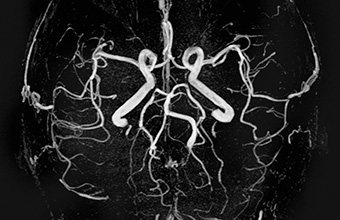

MR žila mozga i vrata

MR angiografija - snimanje žila mozga i vrata - otkriva bolesti širokim spektrom tehnika koristeći napredne kontrastne i nekontrastne metode.